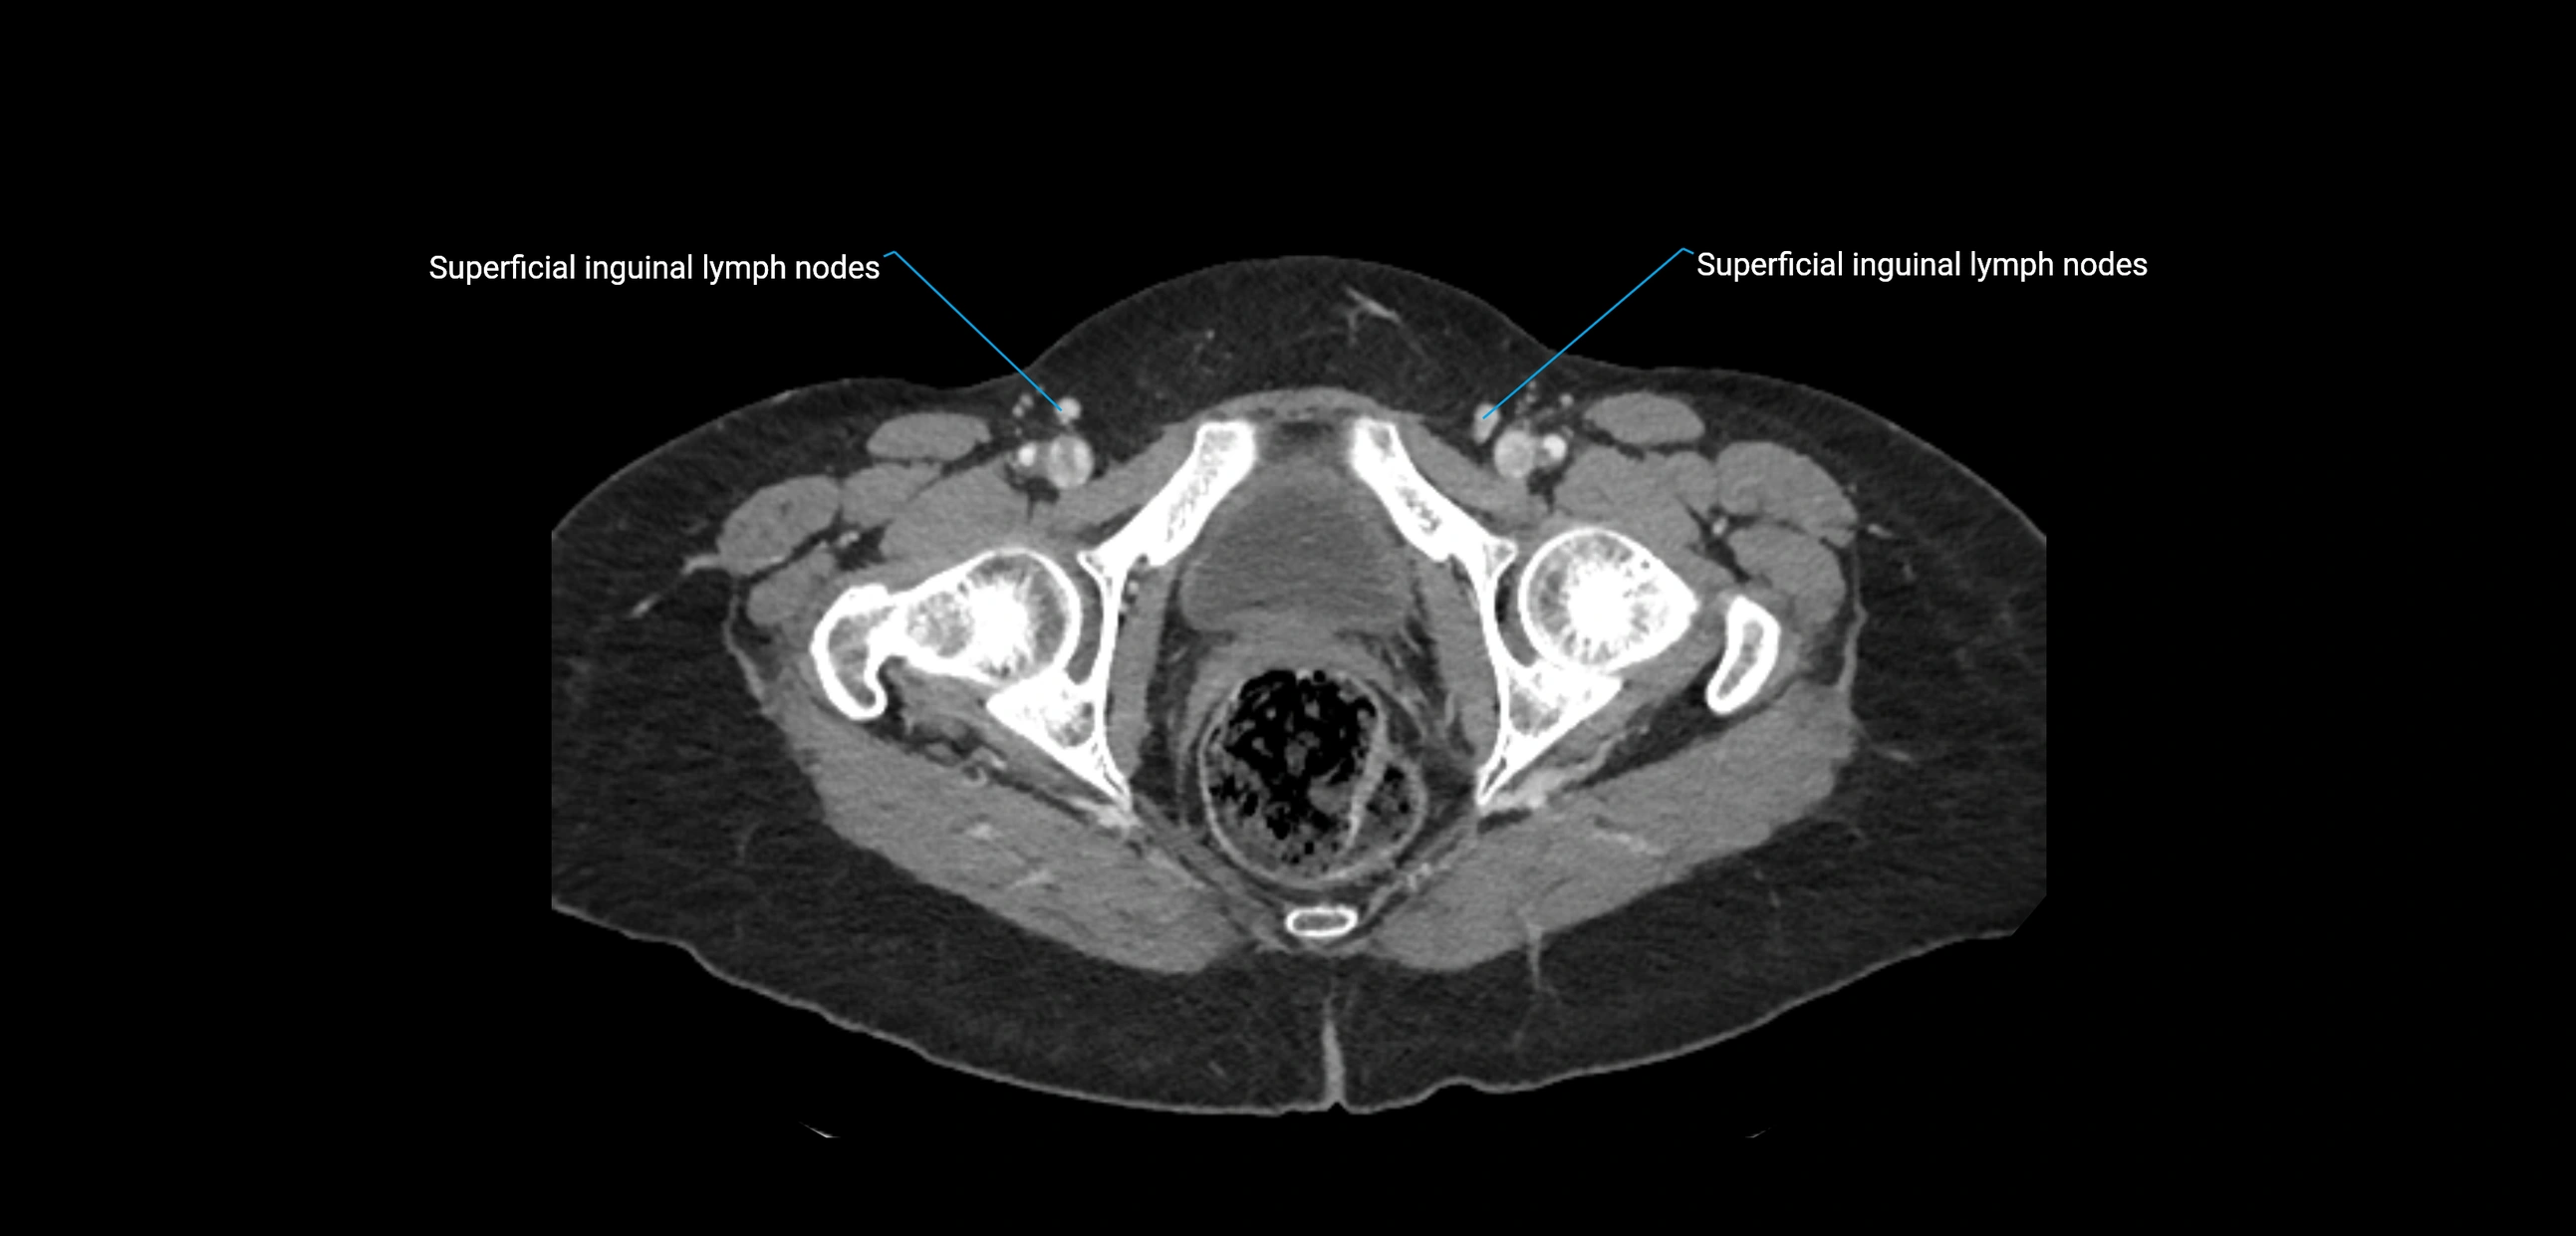

CT Appearance

CT Pre-Contrast:

• Nodes appear as soft-tissue density nodules adjacent to the aorta and IVC

• Calcification may be seen in chronic infections (e.g., tuberculosis)

CT Post-Contrast:

• Normal nodes enhance homogeneously

• Malignant nodes may show heterogeneous enhancement, central necrosis, or conglomerate formation

• Size >1 cm short axis is suspicious, though morphology and distribution are equally important

CT image

image